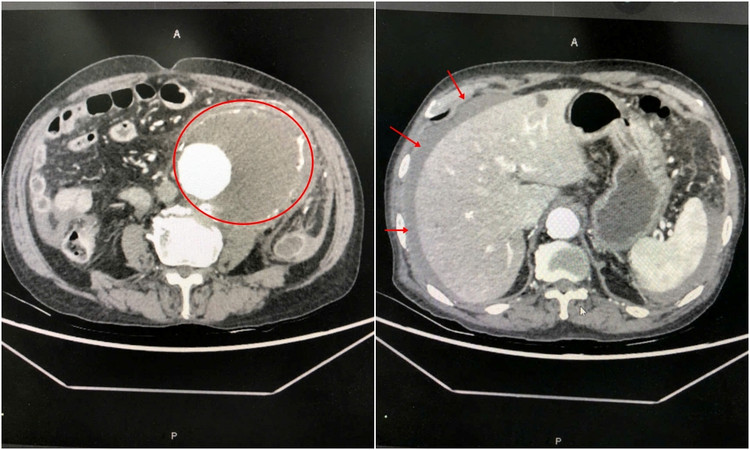

![]() |

| Bác sĩ khoa Ngoại kiểm tra lại vết mổ cho cụ ông 85 tuổi bị vỡ phình động mạch chủ bụng - Ảnh BVCC |